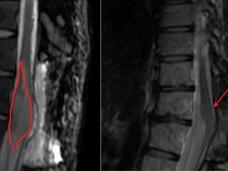

Experimental CAR T-Cell Therapy Shrinks Tumors in Children with Deadly Brain Cancer

In a small clinical trial, an experimental CAR T-cell therapy that targets the protein GD2 on cancer cells shrank tumors—for 2 years or more in several cases—in children and young adults with diffuse midline glioma, an aggressive brain and spinal cord cancer.